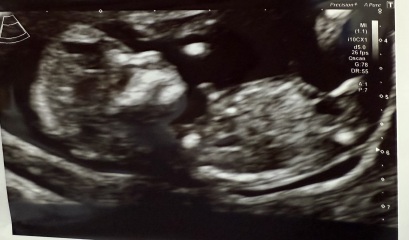

Rainbowbaby25 · 01/06/2025 11:54

Mixed opinions on other forums.

Girl because of bladder position and forked nub, also under 30 degrees and only slightly upward.

Others saying boy because of skull and the nub pointing more up then parrell but not to spine.

12+4 scan